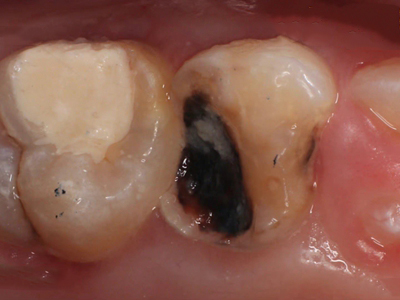

年轻恒牙龋指的是儿童萌出不久的第一恒磨牙龋病和上颌恒切牙龋病,其中第一恒磨牙龋病占年轻恒牙龋的90%,发病早,进展快,可表现为白垩色斑片、点隙窝沟墨浸状龋坏或龋洞。本病的发生和年轻恒牙的特点以及儿童饮食、口腔卫生等因素有关。

年轻恒牙龋好发于第一、二恒磨牙(牙合)面、邻面,上颌中切牙邻面,多为急性龋,龋坏进展快。平滑面的早期龋多为白垩色的斑片,点隙窝沟的早期龋多为浸墨状,表面粗糙。如果早期龋不及时治疗,可逐渐形成大而深的龋洞,易导致牙髓炎和根尖周炎。